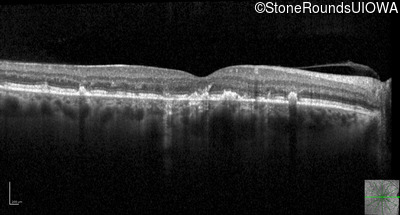

Optical Coherence Tomography - Right - 20/40 +2 sc

Exemplar / OCT Stack